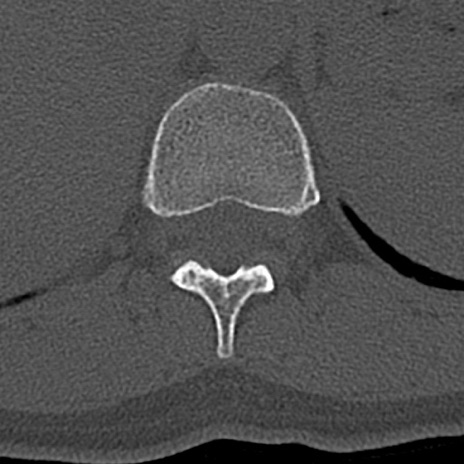

腰椎CT

横断像と矢状断像